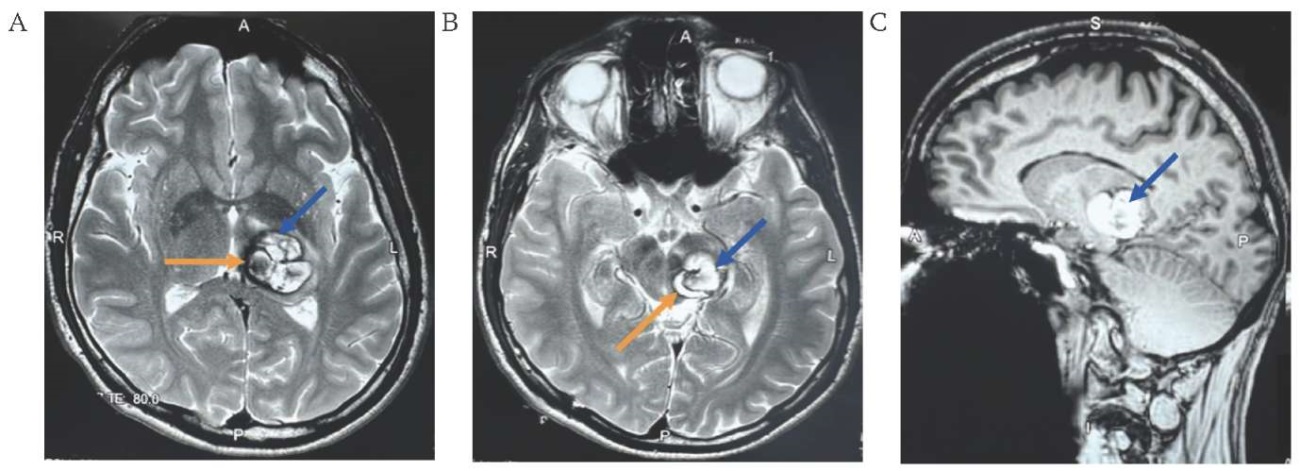

Computed tomography (CT) of the brain revealed a poorly defined hyperdense formation in the lower part of the dorsal surface of the left peduncle of the midbrain measuring 20x30x25 mm. MRI of the brain revealed a hyperintense lesion in T1- and T2-weighted images with a clearly defined hypointense rim, hematomas in a cavernoma of 20×30×25 mm (Fig. 1A–C).

FIG. 1. Magnetic resonance imaging of a 38-year-old patient with a cavernous malformation measuring 20×30×25 mm in the dorsal part of the left peduncle of the midbrain (May 13, 2024).

A, B. Axial sections, T2-weighted image: cavernous malformation (blue arrow), hematomas in the cavernoma (orange arrow).

C. Sagittal section, T1-weighted image: cavernous malformation (arrow).